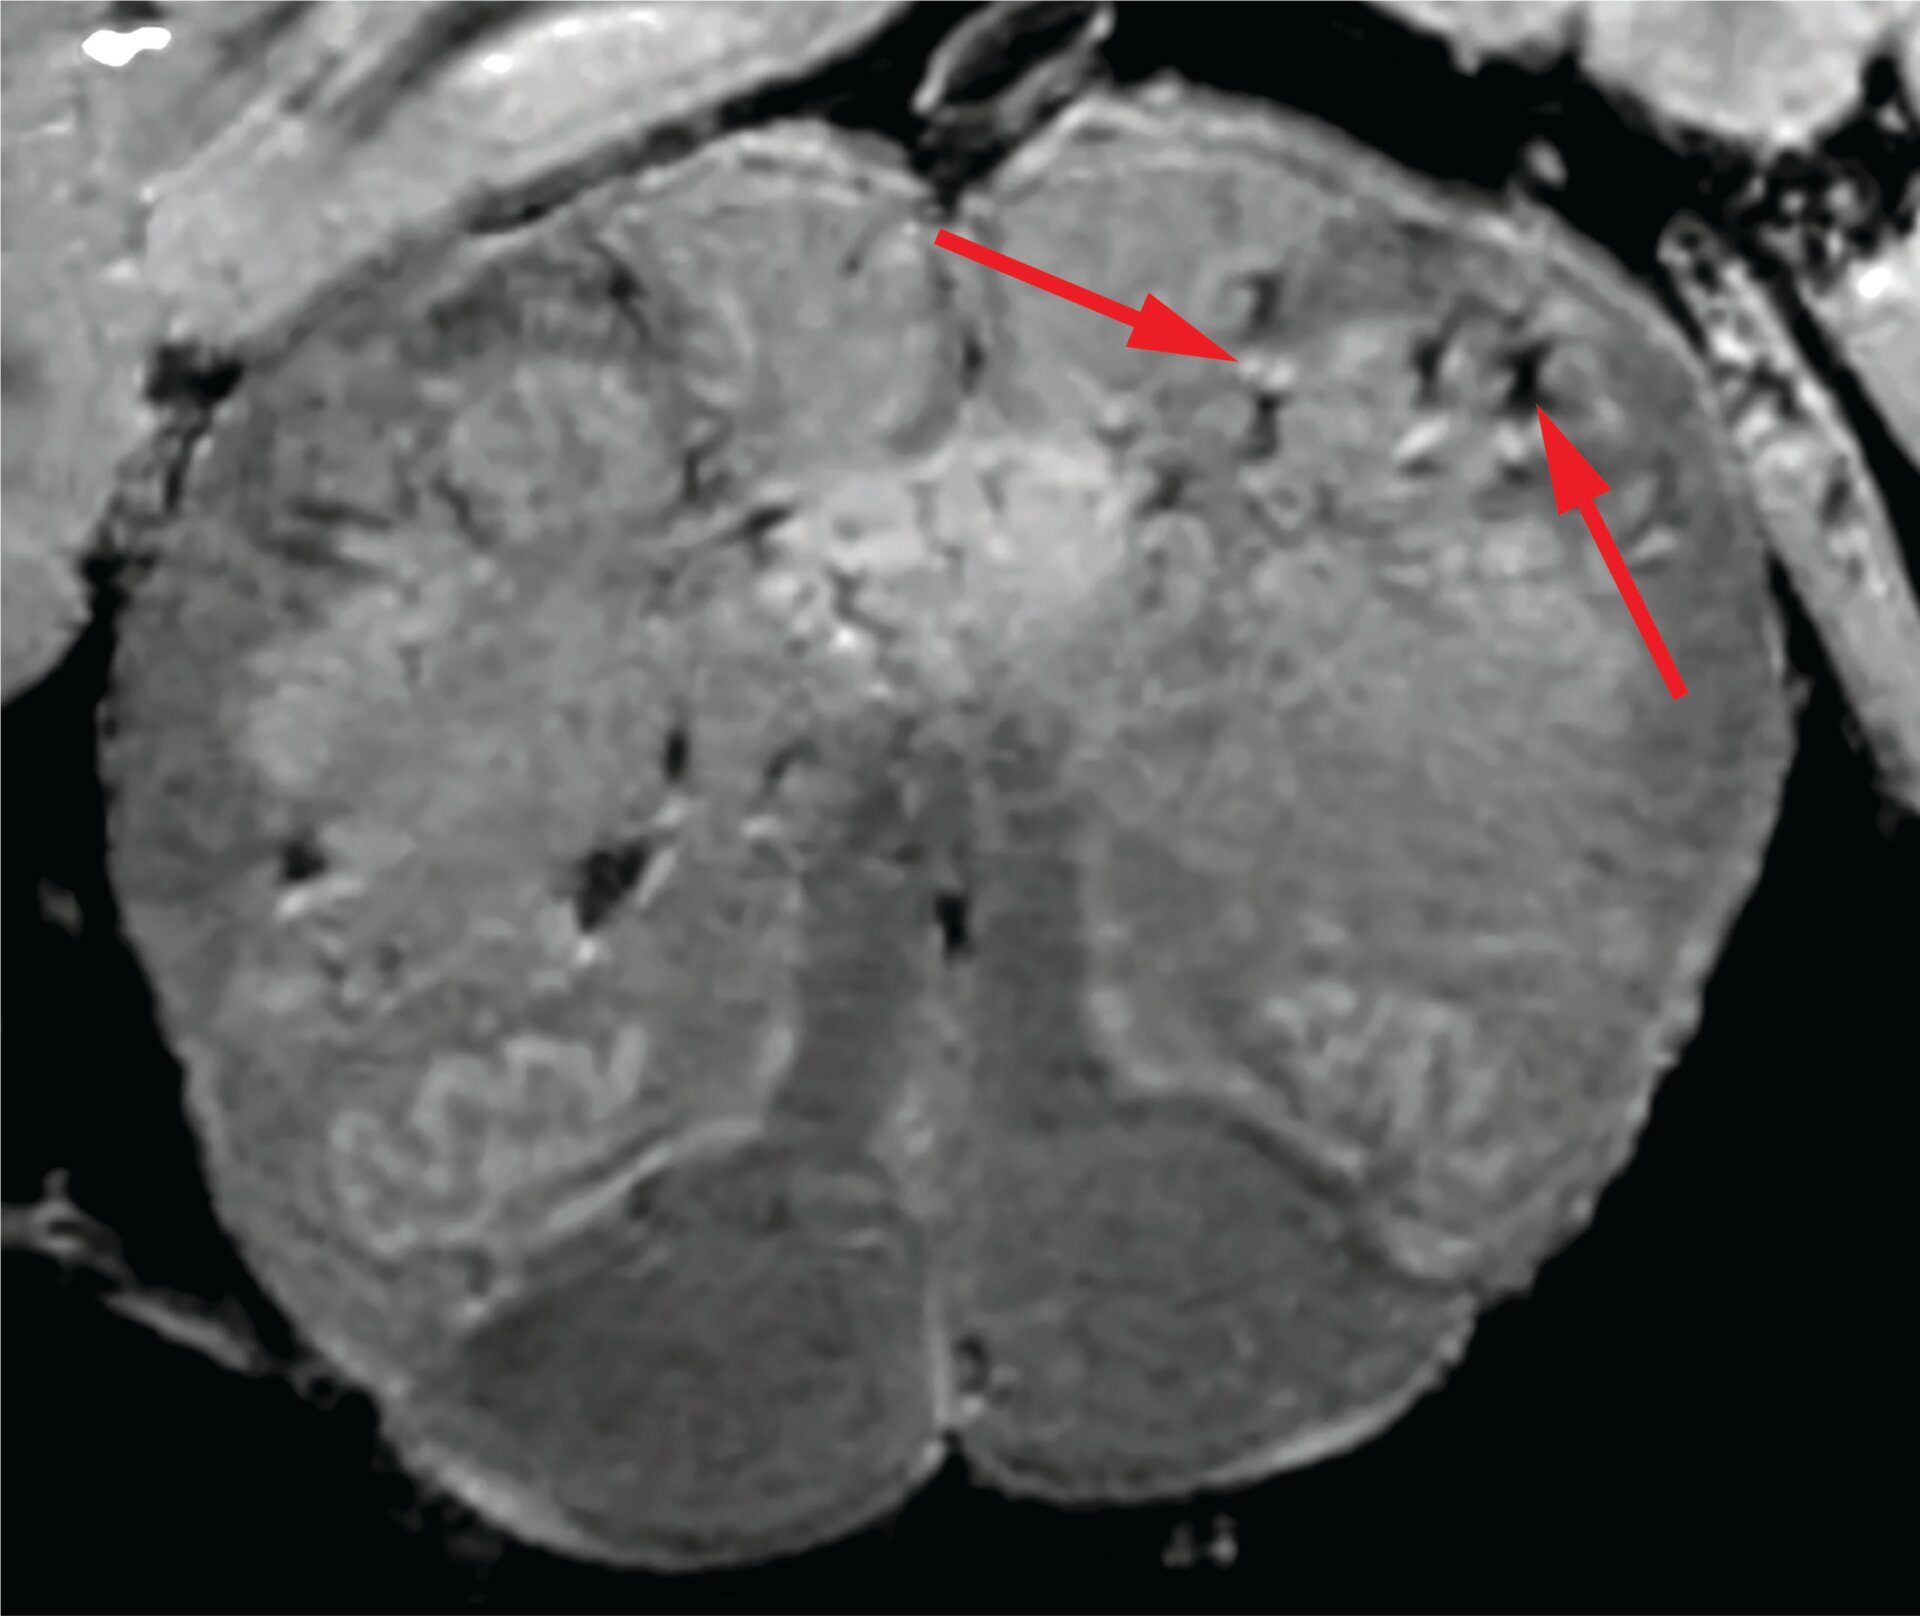

The research was conducted by U.S. government scientists at the National Institutes of Health and is published in the New England Journal of Medicine. The team studied the brains of 19 people who died after contracting covid-19, using highly sensitive MRI scans as well as looking at brain tissue underneath a microscope. These patients ranged in age from 5 to 73 years old, with some having existing health problems like diabetes and cardiovascular disease.

The researchers couldn’t find any traces of the virus in these samples, indicating that it hadn’t infected the brain. But they did find clogged, thinned out, and leaky blood vessels. Near some of these vessels, they also found signs of inflammation, like higher levels of immune cells in the brain called microglia. All told, the findings point to these patients and others like them developing a faulty immune response that attacks the brain’s blood vessels—a response that’s brought on by infection from the coronavirus.

“We were completely surprised. Originally, we expected to see damage that is caused by a lack of oxygen. Instead, we saw multifocal areas of damage that is usually associated with strokes and neuroinflammatory diseases,” said senior study author Avindra Nath, clinical director at the NIH’s National Institute of Neurological Disorders and Stroke, in a statement released by the NIH.